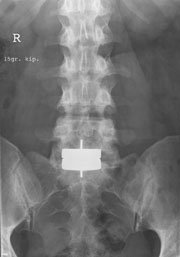

Flere protese-designs har været anvendt. Det mest almindelige anvendte design i dag er protese med metal-backing med eller uden polyethylendel, ganske lig protese-designs anvendt i knækirurgien.

På markedet eksisterer der i dag fire forskellige protesetyper, som har udbredt anvendelse. Charité protesen var den første, der blev kommercielt tilgængelig, Prodisc er anvendt fra omkring 1990 og Maverick protesen fra Medtronic er fra ca. år 2000. Øvrige protesetyper er under udvikling og finder stigende anvendelse.